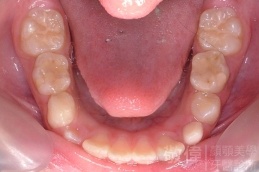

矯正前-上   矯正前-下

矯正後-上   矯正後-下

上顎暴牙且牙齒極度混亂,經由矯正之後,臉型大幅度改善,牙齒的排列更加的整齊健康。相較於之前眼神充滿精神,自信心展現無遺。